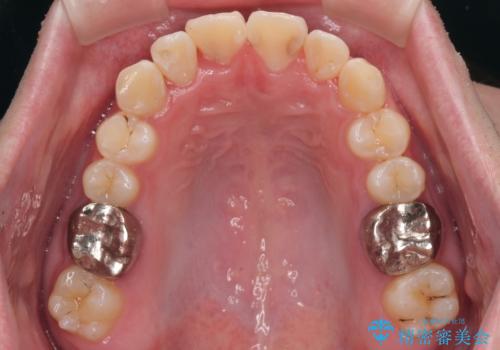

適切な診断と装置の選択により、1年という短期間でここまで改善できます。

見た目の美しさだけでなく、将来のむし歯や歯周病リスクを減らすことにもつながる治療です。